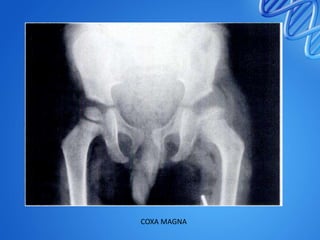

COXA MAGNA

Perthes type hip epiphysio-metaphysealtuberculosis of the left proximal femur (a, b). After joint debridement, the child was immobilized with cast for 6 weeks under cover of triple chemotherapy (12 months). Tuberculosis healed without joint destruction, though residual coxa magna deformity was present (c)